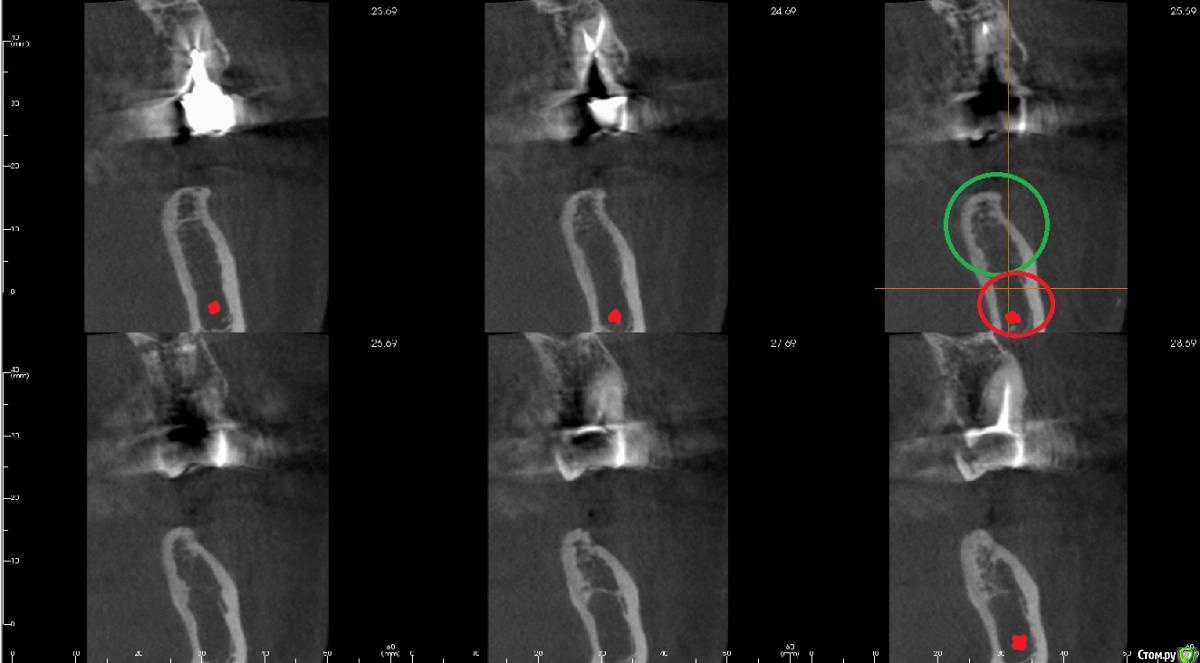

kamranchick Опубликовано 29 марта, 2017 Поделиться Опубликовано 29 марта, 2017 Мой молодой взгляд видит такую картину) 1 Ссылка на комментарий

Irouil Опубликовано 29 марта, 2017 Поделиться Опубликовано 29 марта, 2017 На первом срезе (левый верхний) я на 99% уверен что канал видно - слишком уж правильный контур. Плюс я бы, конечно, все таки с мезио-дистального среза пошел, как и Антон советовал - имея первую реперную точку на вестибуло-оральном срезе и отстреливаясь выше нижней стенки можно построить пусть и не идеально, но примерно канал Ссылка на комментарий

bullbull Опубликовано 30 марта, 2017 Автор Поделиться Опубликовано 30 марта, 2017 Я при повторном осмотре выставил примерно так. Может перестраховка. Но 4.0.10 становятся неплохо.Такая низкая плотность не является патологией? Ссылка на комментарий

Bier Опубликовано 30 марта, 2017 Поделиться Опубликовано 30 марта, 2017 не является. Но разумеется сверлить по протоколу тут не надо.Я бы может только пилотом на всю глубину и потом только кортикальный слой расширить. 1 Ссылка на комментарий